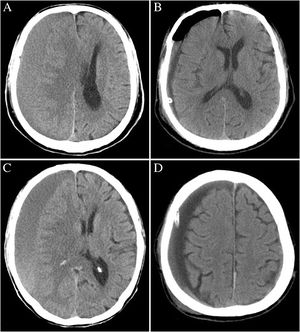

A Comparative Study of Irrigation Versus no Irrigation during Burr Hole Craniostomy to Treat Chronic Subdural Hematoma

Publication: BMC Surg. 2017 Sep 11;17(1):99. PMID: 28893217 | PDF Authors: Wang QP, Yuan Y, Guan JW, Jiang XB. Institution: Department of Neurosurgery, Union Hospital, Tongji Medical College, Huazhong University of Science and Technology, Wuhan, China. Abstract: Background: Burr hole craniostomy is a widely used method for the evacuation of CSDH. However it is not clear whether the irrigation during operation improves the prognosis or gives rise to additional complications instead. This retrospective cohort study was conducted to determine this issue. Methods: Patients attending two medical centers in China who underwent burr hole drainage with irrigation (BHDI) or burr hole drainage without irrigation (BHD) for unilateral CSDH during January 2013 to December 2016 were included in this study. The patients' clinical information and follow-up data were retrospectively reviewed, and the radiologic findings were processed using the 3D Slicer software. The differences in outcomes were identified using t-test, chi-square test, or Fisher's exact test. Results: A total of 151 patients comprising 63 patients in the BHD group and 88 patients in the BHDI group were included. Patients in the BHDI group had a higher volume of pneumocrania on the first postoperative day than that of patients in the BHD group (p < 0.05). No significant differences were observed between the two approaches in rates of rebleeding, recurrence and other complications (p > 0.05). Conclusions: Irrigation had no improvement in the long-term curative effect on CSDH, but it increased the risk of short-term complication in terms of pneumocrania. Therefore, this study suggests that irrigation is not an obligatory procedure during burr hole drainage. |

CT scans of two typical patients undergoing BHD and BHDI. a and b are the preoperative and first postoperative day images of a patient receiving BHDI, respectively. c and d are the preoperative and first postoperative day images of a patient receiving BHD, respectively. Obvious pneumocrania can be observed in image b. This image is from the preliminary report of the present study, which was published in West China Medicine Journal [27]. The authors have got the permission to republish this image. |